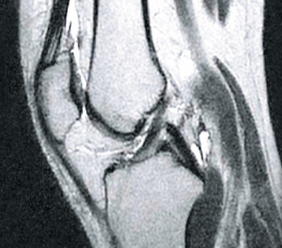

POSLIJE

Na slici lijevo vidljivi su prazni prostori unutar zglobne čahure nastali zbog prekomjernog nakupljanja tekućine u tkivu. Nakon tretmana, struktura sinovijalne tekućine se obnovila (slika desno), povratila viskozno-elastičnu konzistenciju i svojstva podmazivanja. Kosti su pravilno "podmazane", zahvaljujući čemu se ne strugaju jedna o drugu, jer su obnovljene amortizacijske funkcije zgloba.